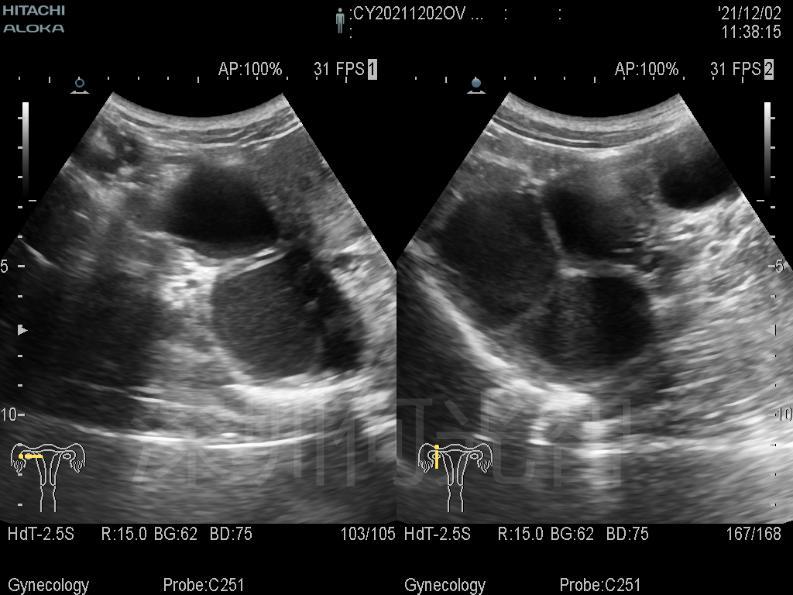

图1:M小姐右侧卵巢内多发巧囊,最大一个直径5公分。

按照预约时间,M小姐来到了何光智主任的介入超声专家门诊。通过详细询问病史,查阅过往检查结果,现场超声检查,确认了右侧附件区有三个囊肿,其中靠近深部的两个囊肿(巧囊1与巧囊2),大小分别为55×52×46mm(超声估测70mL)、36×34×35mm(超声估测22mL),靠近浅部的一个大小为33×32×27mm(超声估测14mL),确实需要治疗。